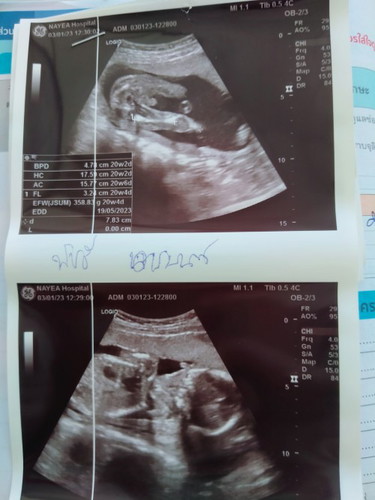

ช่วยดูหน่อยคะหมอบอกผู้หญิงไม่มั่นใจเลยคะ #ท้องเเรก